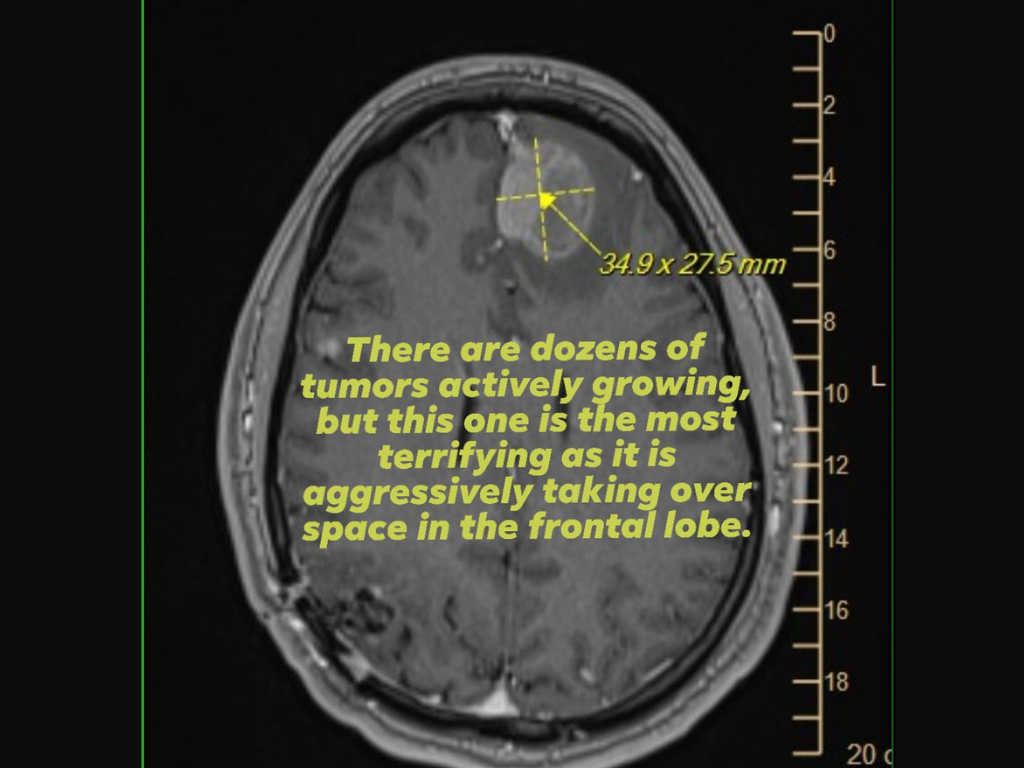

Als Beleg veröffentlichte sie außerdem ein Bild einer MRT-Aufnahme des Gehirns, auf der ein aggressiver Tumor im Frontallappen zu sehen ist, und wandte sich mit der Bitte um Unterstützung an die Führungsebene von Epic Games, die die maßgeblichen Entscheidungen zu den Entlassungen getroffen hatte.